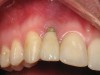

Figure 2  Clinical photograph of an implant restoration replacing the congenitally missing maxillary left lateral incisor. Note the cyanotic color changes, due to inflammation and cement, of the marginal gingiva in a 31-year-old female patient with thin biotype.

Figure 2